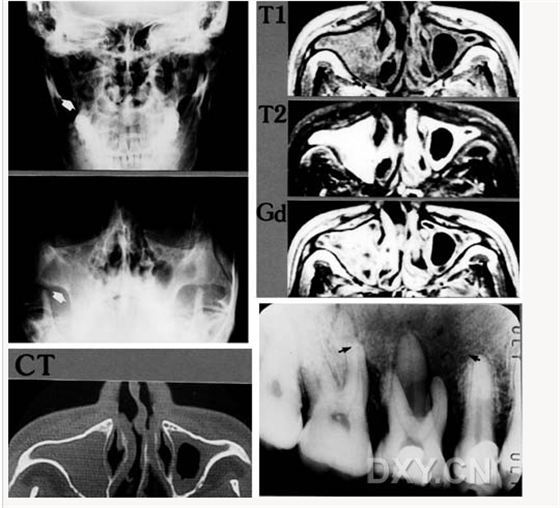

鼻鄂囊腫

根尖囊腫

骨肉瘤

涎石病

頜骨纖維性結(jié)構(gòu)不良癥

鼻腭囊腫

鼻竇炎(注意不要誤診呀)